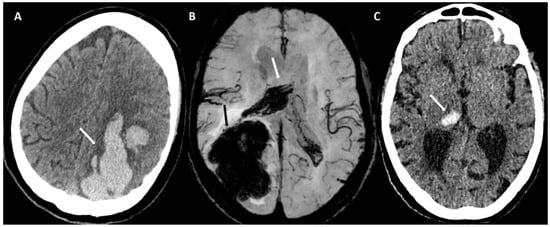

6.1. Finger-like Projections

6.2. Subarachnoid Extension of Lobar Hemorrhage

- Baron, J.-C.; Boulouis, G.; Benzakoun, J.; Schwall, C.; Oppenheim, C.; Turc, G.; Varlet, P. Cerebral amyloid angiopathy-related acute lobar intra-cerebral hemorrhage: Diagnostic value of plain CT. J. Neurol. 2022, 269, 2126–2132. [Google Scholar] [CrossRef]

- Baron, J.-C.; Jensen-Kondering, U.; Sacco, S.; Posener, S.; Benzakoun, J.; Pallud, J.; Oppenheim, C.; Varlet, P.; Turc, G. Can novel CT-and MR-based neuroimaging biomarkers further improve the etiological diagnosis of lobar intra-cerebral hemorrhage? J. Neurol. 2023, 270, 582–588. [Google Scholar] [CrossRef]